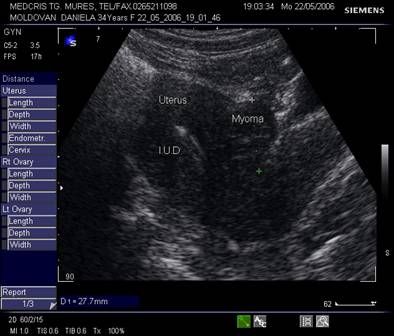

Fibromul uterin - cea mai frecvent intalnita tumora genitala, cu frecventa de 20 - 50% din femei [3].

Aproximativ 90% din fibroame (leiomioame) apar la nivelul corpului uterin. Se descriu, faza miomatozei difuze, fibroame intramurale, subseroase, submucoase, intraligamentare.Mioamele prezinta margini bine delimitate fata de miometru la ecografie, continand arii de mai mare sau mai mica ecogenitate in functie de modificarile degenerative.[1,6]

Fig, nr.380. Nodul fibromatos intramural si subseros al peretelui anterior uterin, in sectiunea sagitala a ecografiei abdominale